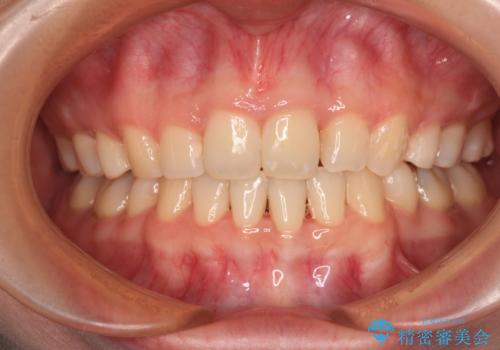

舌の突出癖の影響もあり、非抜歯矯正で治療開始したものの口元が突出し、唇が閉じにくくなってしまったため、途中で第一小臼歯4本を抜歯ししました。

口元の突出感のない、すっきりとした仕上がりとなりました。